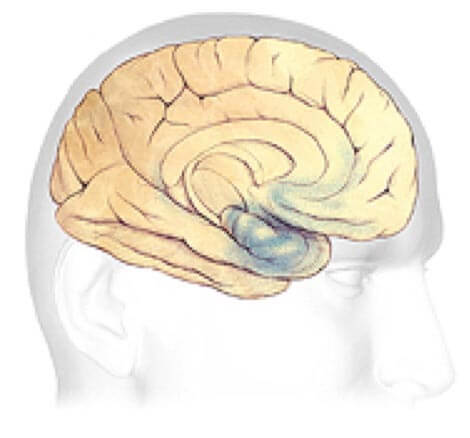

Alzheimer's disease leads to nerve cell death and tissue loss throughout the brain. Over time, the brain shrinks dramatically, affecting nearly all its functions.

These images show:

A brain without the disease.

Progression Through the Brain

Plaques and tangles (shown in the blue-shaded areas) tend to spread through the cortex in a predictable pattern as Alzheimer's disease progresses. The rate of progression varies greatly. On average, a person with Alzheimer's lives four to eight years after diagnosis, but can live as long as 20 years, depending on other factors. The course of the disease depends in part on age at diagnosis and whether a person has other health conditions.

Earliest Alzheimer's - changes may begin 20 years or more before diagnosis.

Earliest Alzheimer's Stages

In the earliest stages, before symptoms can be detected with current tests, plaques and tangles begin to form in brain areas involved in:

Learning and Memory

Thinking and Planning